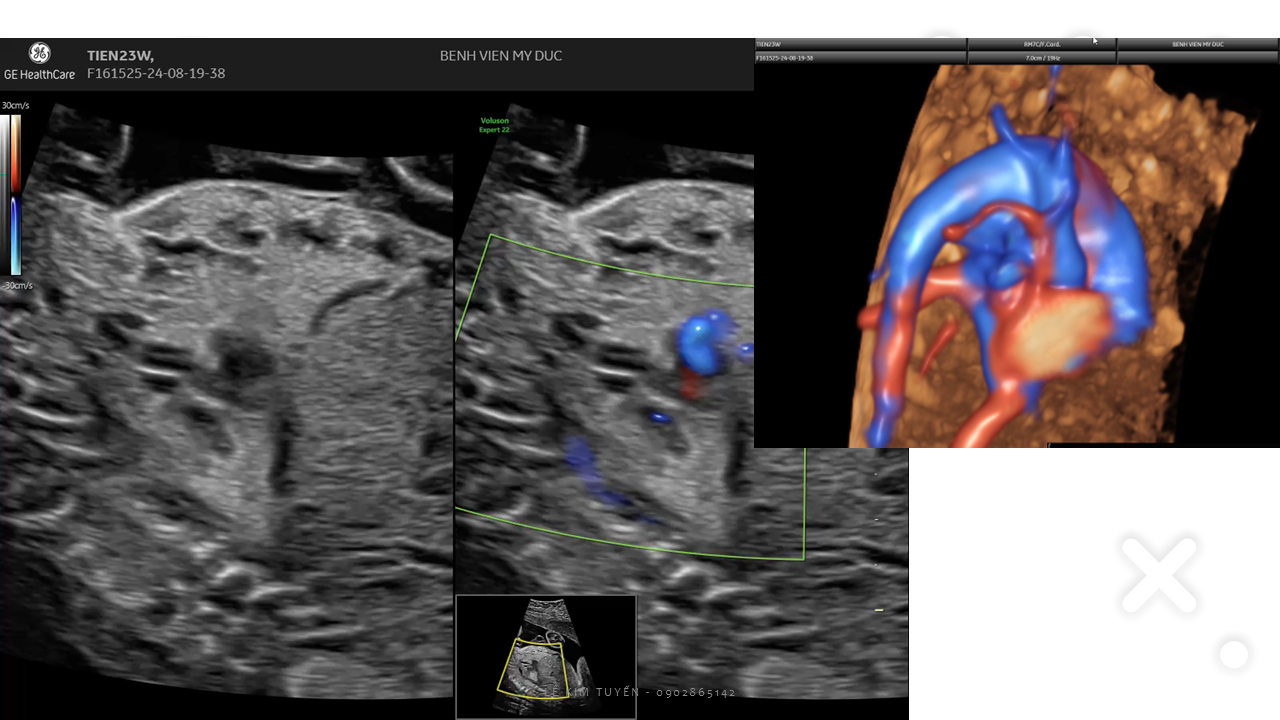

Siêu âm tim thai - Các kỹ thuật hiện đại

TS. BS. Lê Kim Tuyến

Bệnh viện Tim Tâm Đức